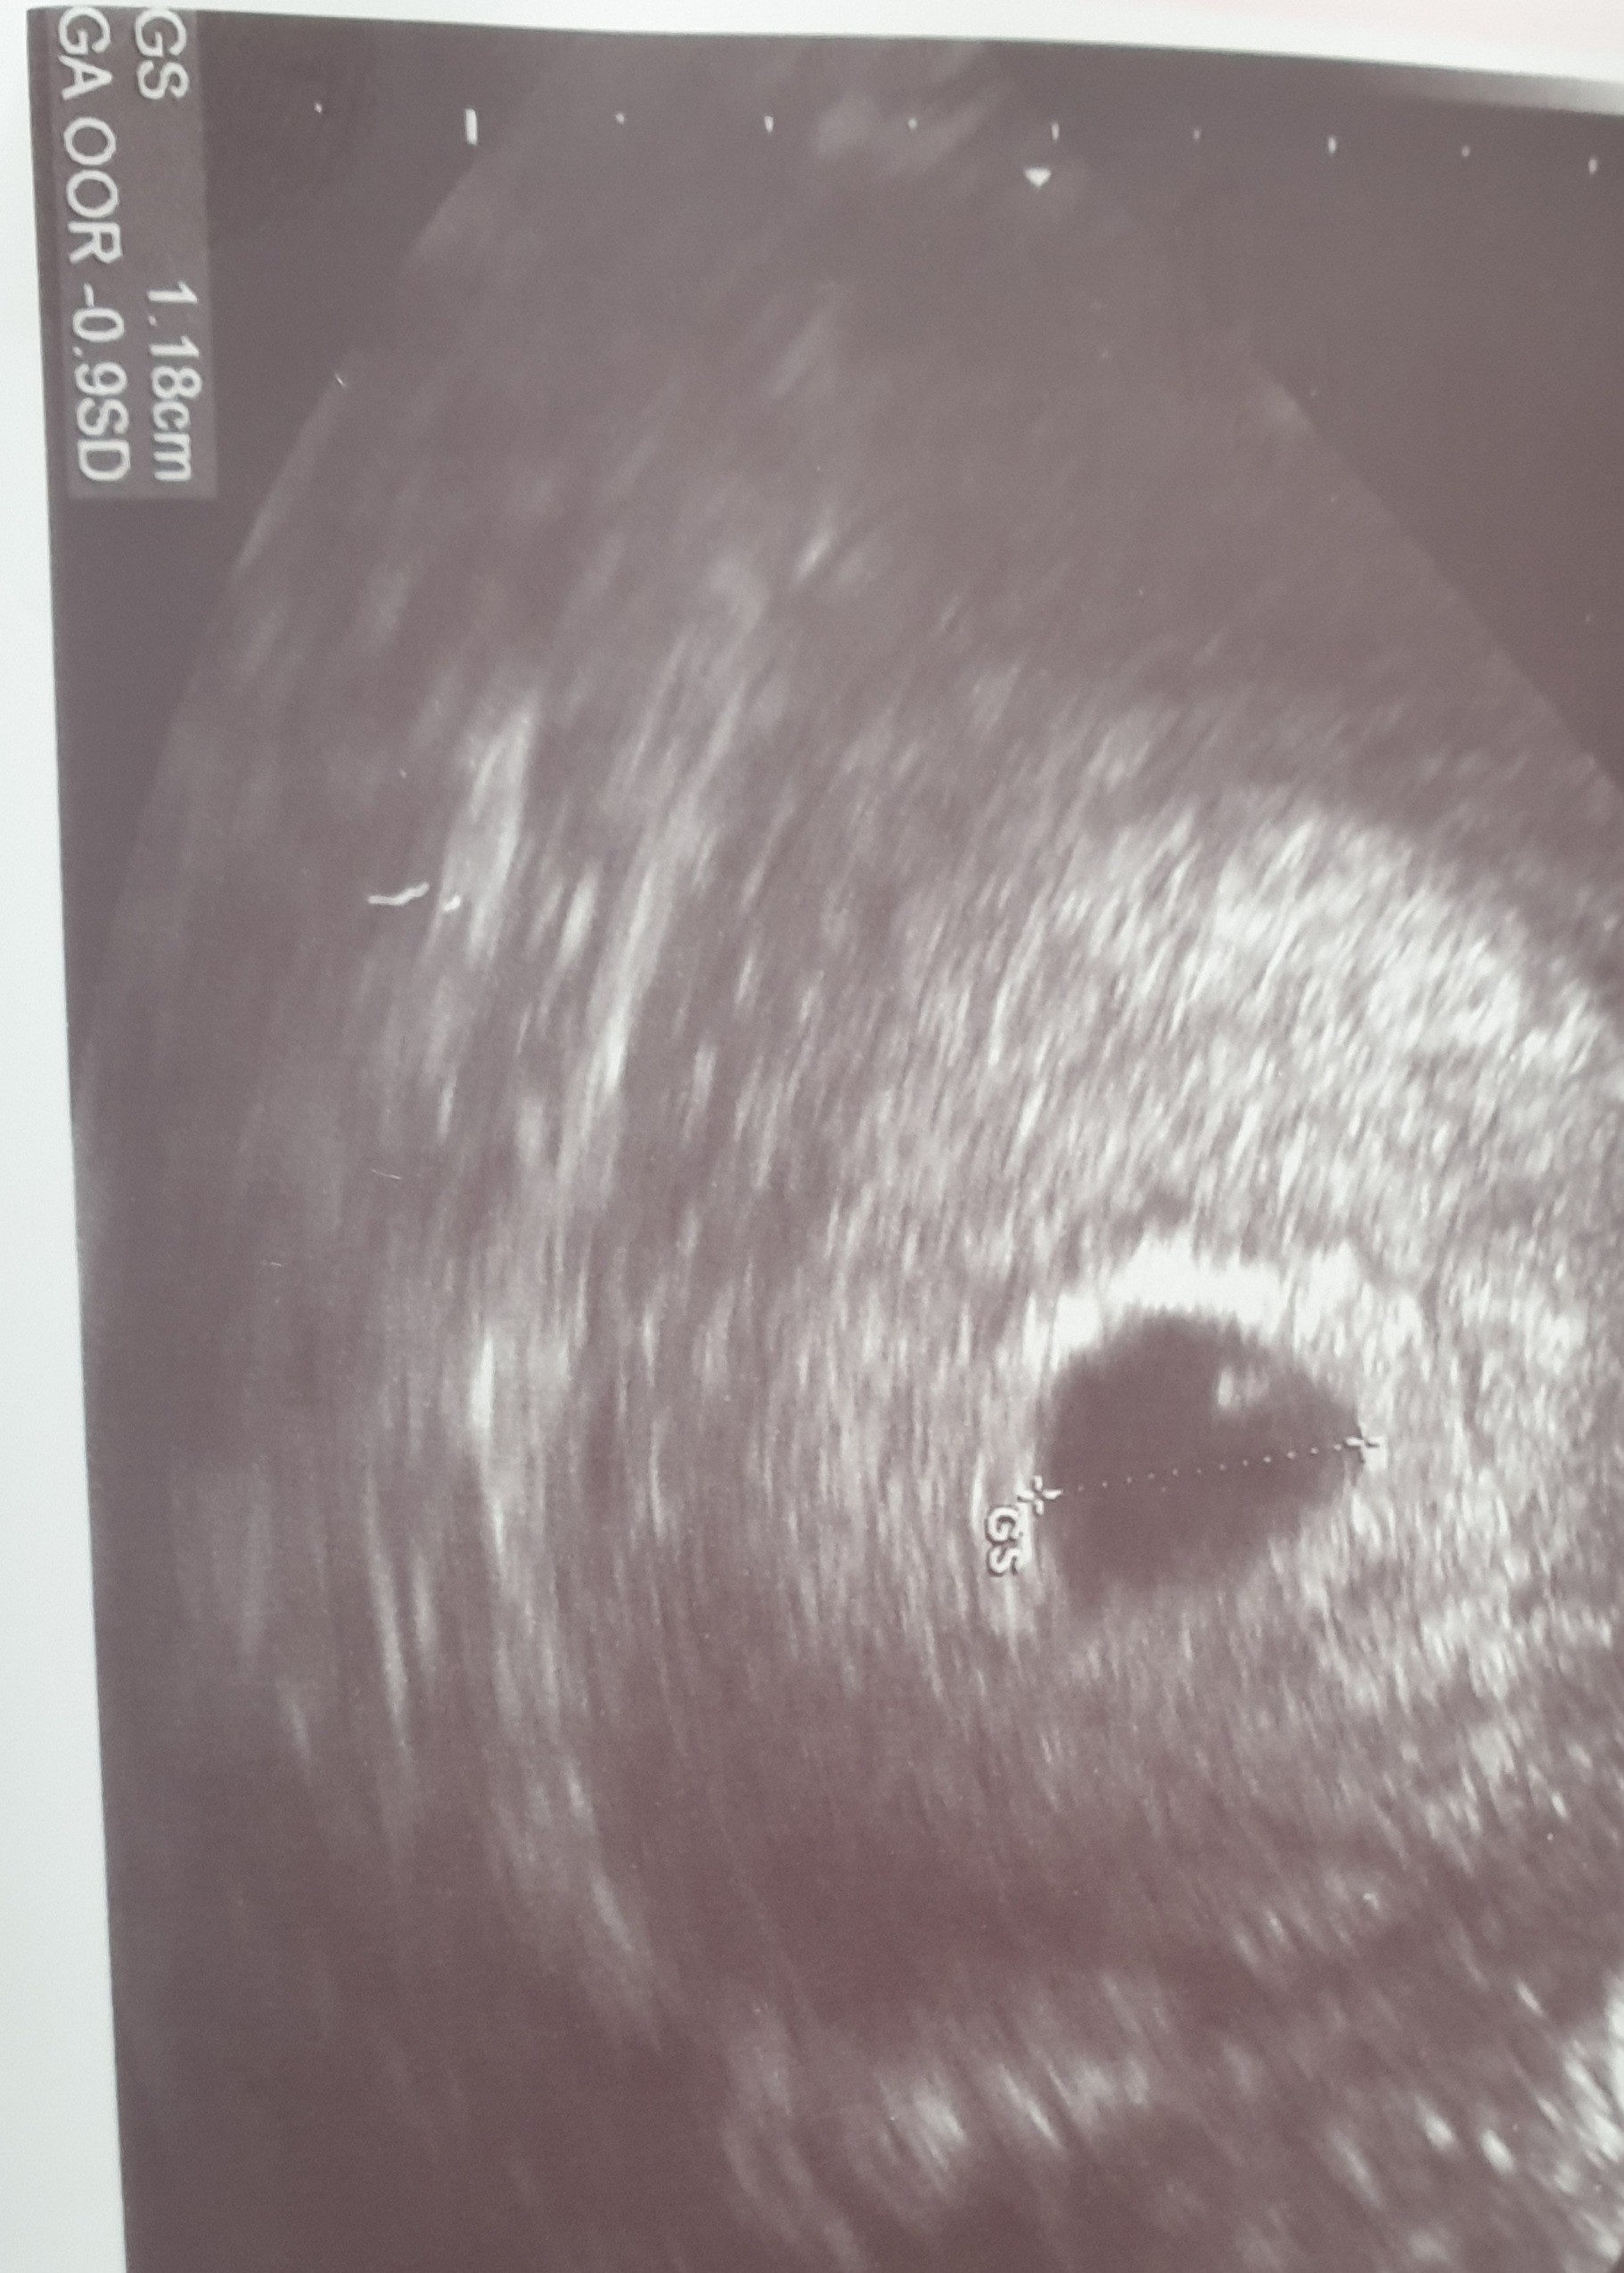

Jak jest pęcherzyk zółtkowy to będzie zarodek :-) yupi!Jest pęcherzyk.

I jakaś malutka kropka w środku.

Pieknie ! Na serduszko wczesnie wiec się nie stresuj. Kiedy powtórka usg?Jest pęcherzyk.

Będzie z tego dziecie [emoji7] niech się rozwija dobrze [emoji120]Jest pęcherzyk.

Zobaczymy, tego w środku nie mierzył za małe.Jak jest pęcherzyk zółtkowy to będzie zarodek :-) yupi!

Wiesz ja tak ostrożnie po tym pustym jaju podchodzę boję się nakręcać, potem wydaje mi się, że bardziej boli.

Dopiero za 10 dni ;(.Pieknie ! Na serduszko wczesnie wiec się nie stresuj. Kiedy powtórka usg?